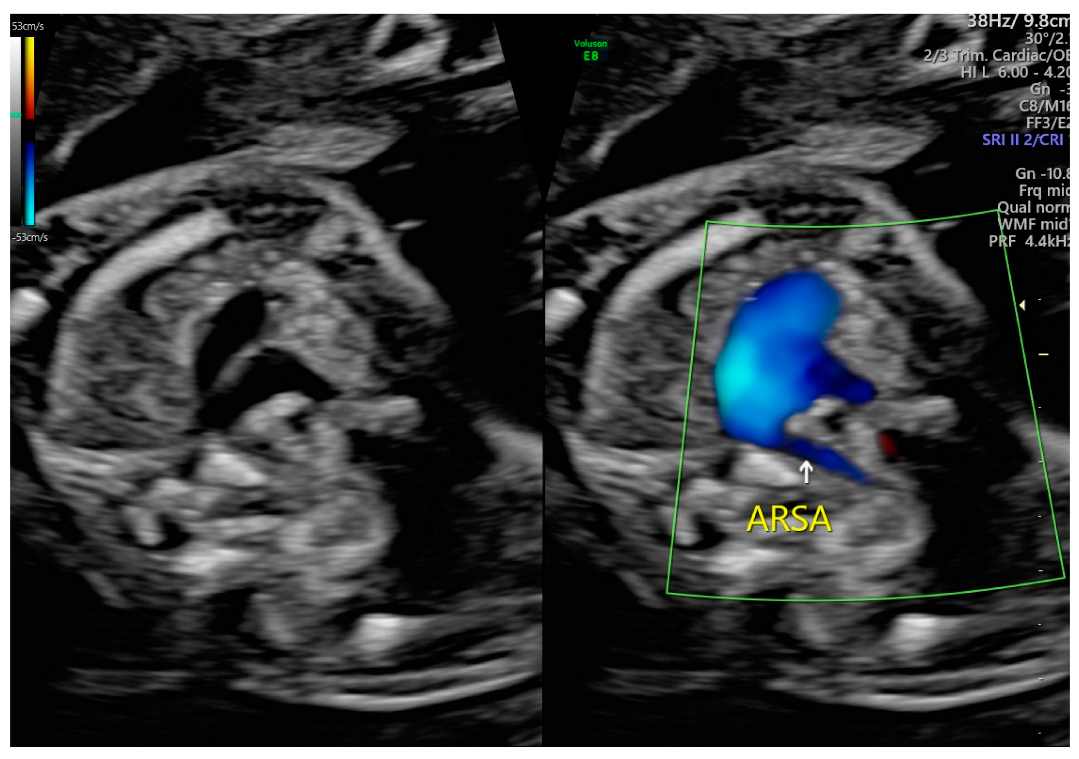

Comprehensive Analysis of the Aberrant Right Subclavian Artery: A Perspective from a Single Institute

4.1. Prenatal Diagnostic Techniques and Standardization